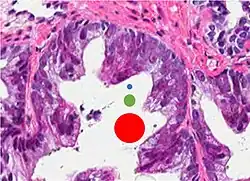

This case could meet the criterion of six times normal nuclear size for intraductal carcinoma of the prostate if size is defined as nuclear area but not if defined as nuclear diameter (blue dot: size of normal nucleus, green dot: size six times normal area and red dot: size six times normal diameter).[20]

Intraductal carcinoma of the prostate gland (IDCP), which is now categorised as a distinct entity by WHO 2016, includes two biologically distinct diseases. IDCP associated with invasive carcinoma (IDCP-inv) generally represents a growth pattern of invasive prostatic adenocarcinoma while the rarely encountered pure IDCP is a precursor of prostate cancer.[20] The diagnostic criterion of nuclear size at least 6 times normal is ambiguous as size could refer to either nuclear area or diameter. If area, then this criterion could be re-defined as nuclear diameter at least three times normal as it is difficult to visually compare area of nuclei.[20] It is also unclear whether IDCP could also include tumors with ductal morphology.[20] There is no consensus whether pure IDCP in needle biopsies should be managed with re-biopsy or radical therapy. A pragmatic approach would be to recommend radical therapy only for extensive pure IDCP that is morphologically unequivocal for high-grade prostate cancer.[20] Active surveillance is not appropriate when low-grade invasive cancer is associated with IDCP, as such patients usually have unsampled high-grade prostatic adenocarcinoma.[20] It is generally recommended that IDCP component of IDCP-inv should be included in tumor extent but not grade.[20] However, there are good arguments in favor of grading IDCP associated with invasive cancer.[20] WHO 2016 recommends that IDCP should not be graded, but it is unclear whether this applies to both pure IDCP and IDCP-inv.[20]